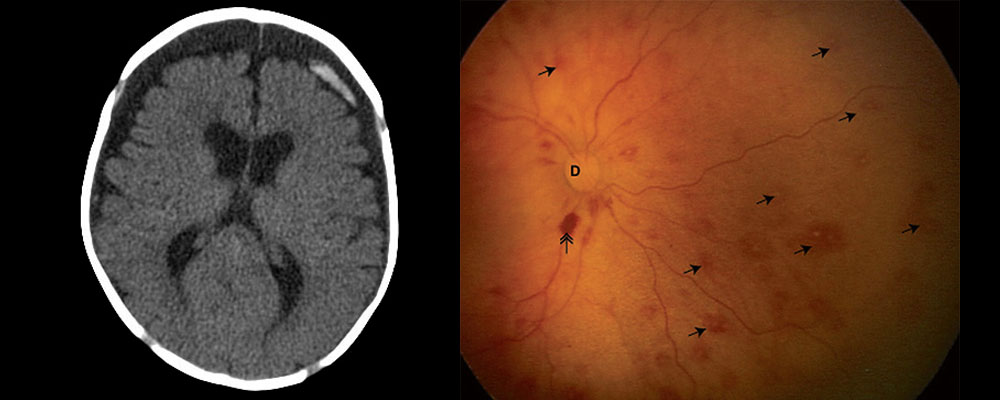

Le syndrome du bébé secoué est défini par la présence d’un hématome sous-dural chez un nourrisson pour lequel l’interrogatoire de l’entourage ne retrouve pas de traumatisme crânien ou retrouve un traumatisme minime probablement incompatible avec les lésions constatées.

L’association d’un hématome sous-dural aigu et d’hémorragies rétiniennes au fond d’œil chez un nourrisson pour lequel aucun traumatisme compatible n’est retrouvé définit le traumatisme crânien non accidentel.

Autrement dit, le « syndrome du bébé secoué » se définit par un bébé qui présente du sang autour du cerveau et/ou au fond des yeux en l'absence de tout traumatisme reconnu.